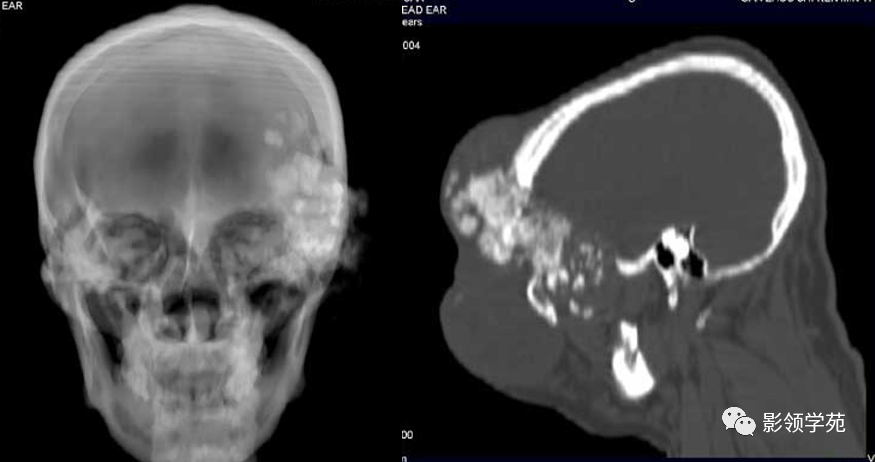

CT诊断:甲状腺癌双肺多发转移